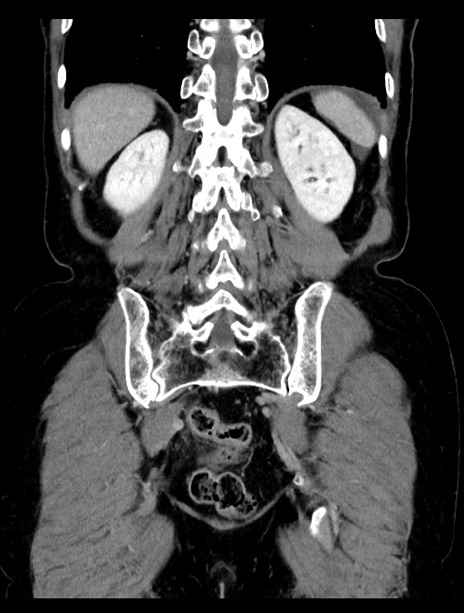

症例23(冠状断像)

【症例】70歳代女性

【主訴】下腹部痛・嘔吐

【現病歴】2日前より腹痛あり。昨日嘔吐あり。症状改善しないため来院。

【既往歴】胃GISTに対して胃部分切除後。

【身体所見】BT 37.1℃、BP 128/77mmHg、腹部:平坦・軟、下腹部に圧痛あり。

【データ】WBC 10200、CRP 0.31